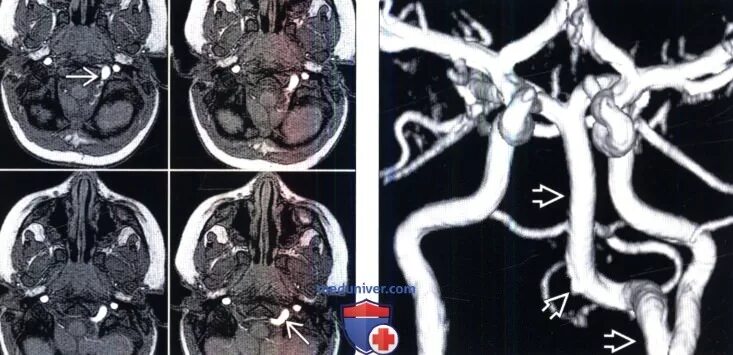

Сегменты вса мрт